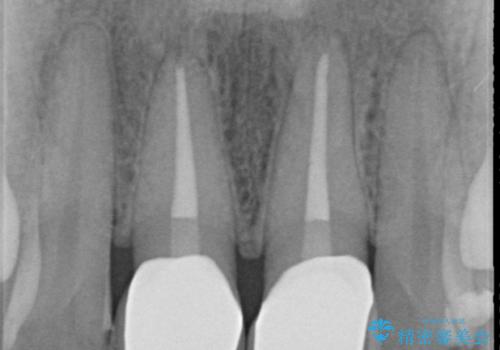

X線検査を行ったところ、共に深い虫歯が原因となり神経が死んでしまっている状態であることがわかり、根管治療を行ったのちセラミック補綴を行っていくこととなりました。

- 32万円(仮歯・ファイバーコア・ジルコニアクラウン×2)費用は治療当時の料金となります

最終的なセラミッククラウンの精度・色調は非常に大事ですが、そこに至るまでの根管内環境の洗浄、ファイバーコアによる緊密な封鎖も長期的な予後に重要であると考えます。